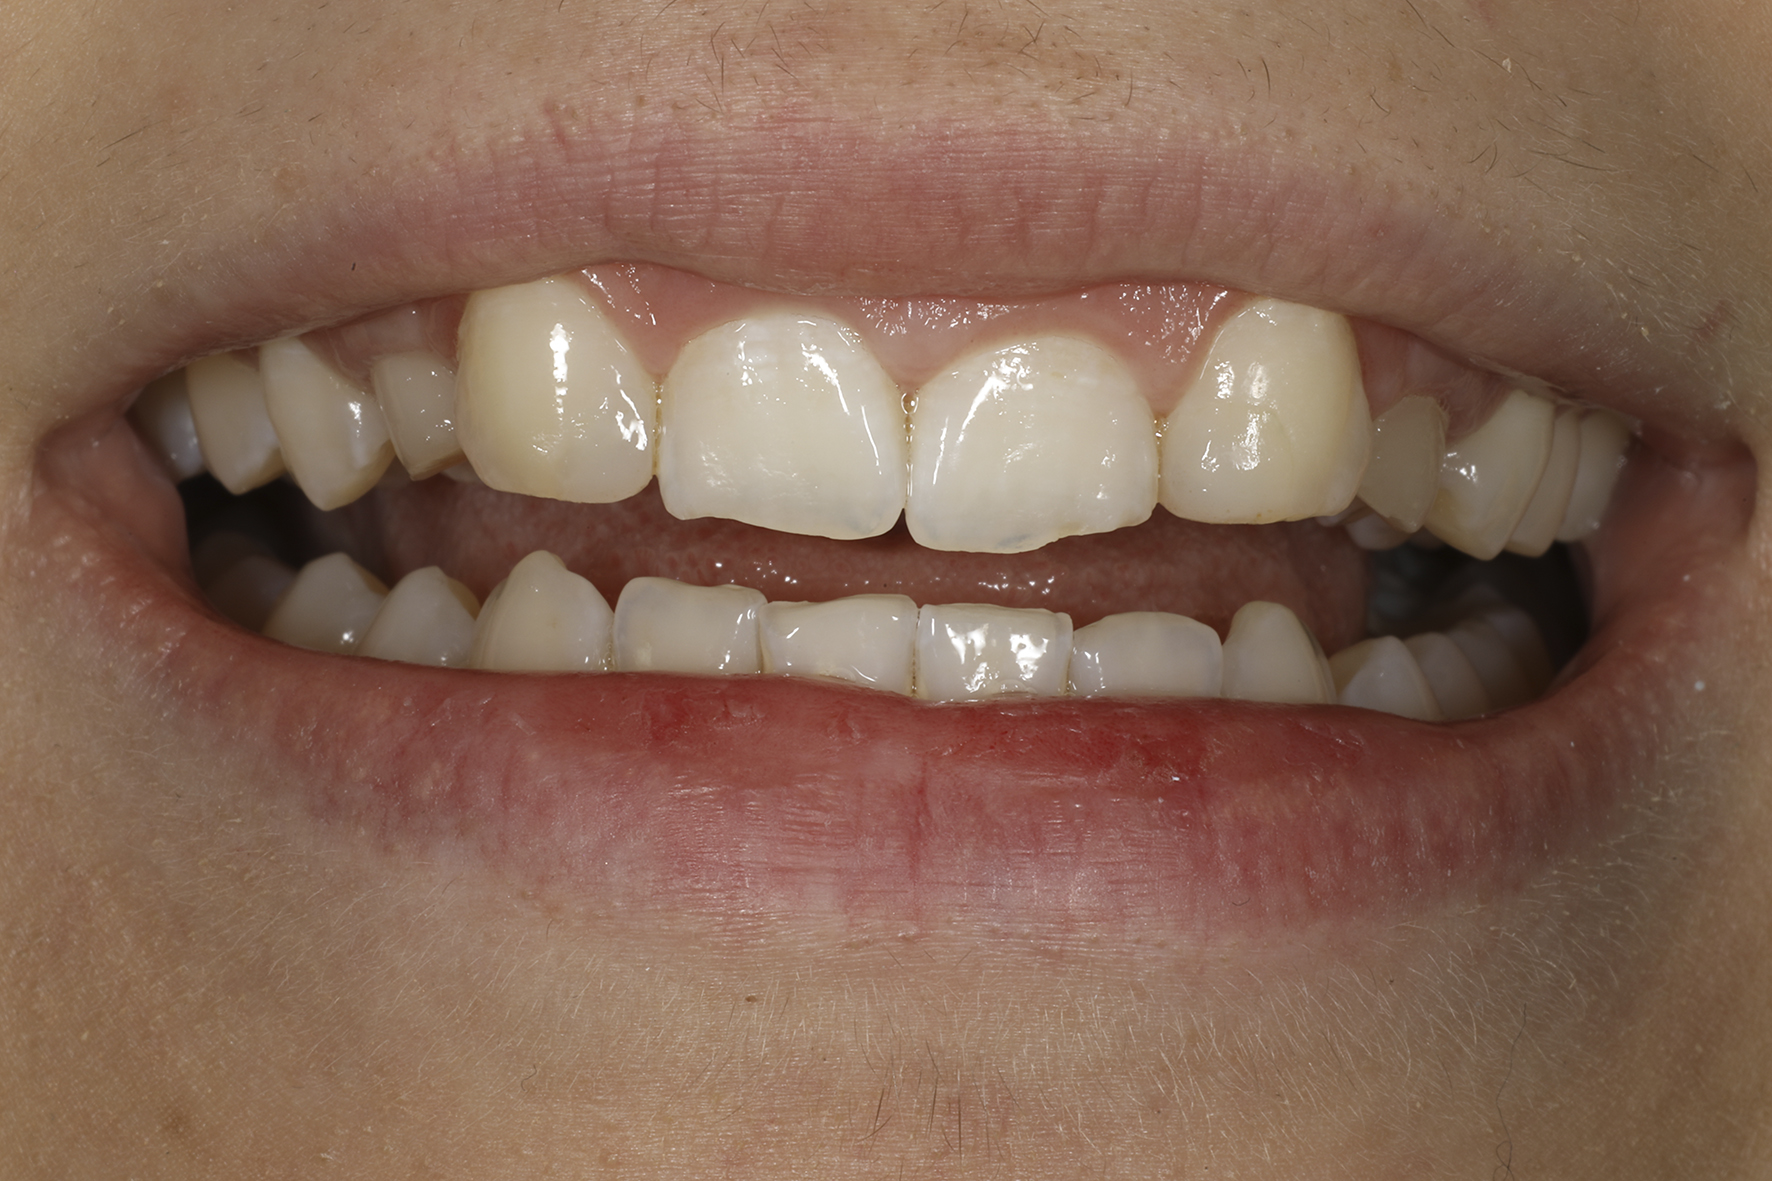

Alkutilanne

Alkutilanne läheltä